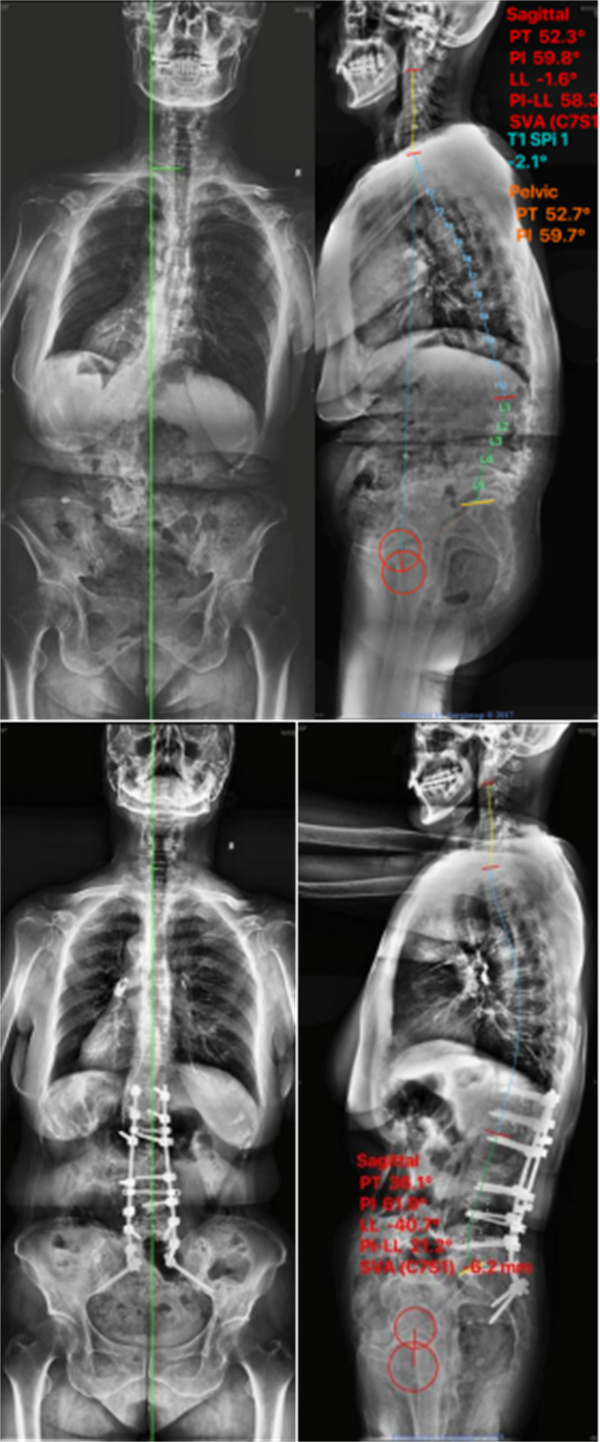

严重强直性脊柱炎后凸

该患者存在严重的脊柱后凸,且颈椎自发融合,无活动度,困难气道,插管难度大。术前体位摆放困难,颈椎、肩关节、髋关节损伤风险较大。术中高级别截骨,脊髓损伤风险较大。手术时间长,出血多,术中需随时调整体位,颈椎损伤风险较大。强制性脊柱炎患者自身免疫力低,椎体骨质疏松,术后感染、螺钉拔出等风险较大。